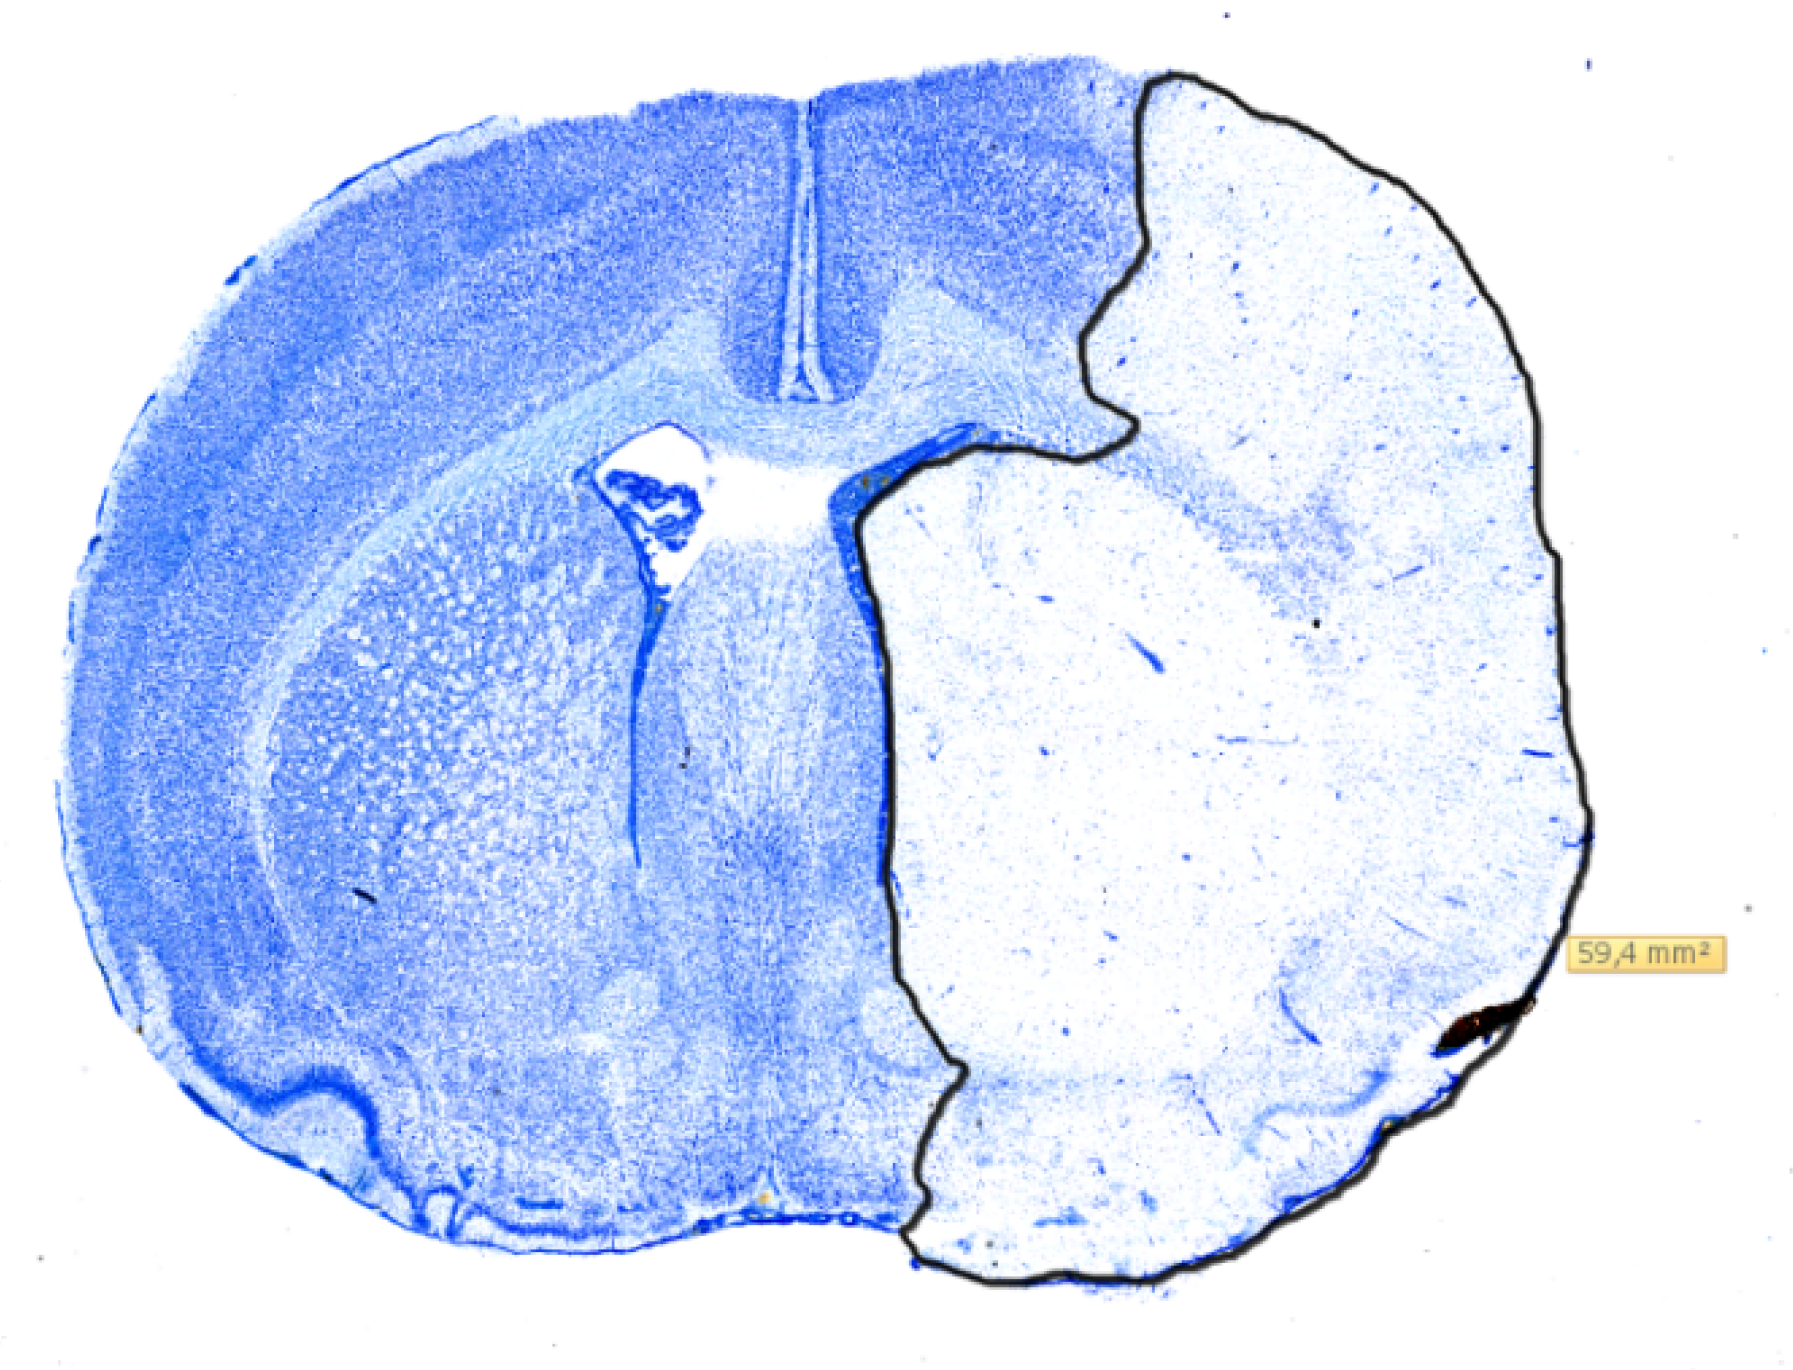

4.4. Infarct Volumetry

The whole rat forebrain was sectioned coronally into 30 µm slices, using a Leica CM 3050S cryostat, and placed on microscope slides. Next, they were stained in Toluidine-blue and digitalized using a pathoslide-scanner (Hamamatsu NanoZoomer 2.0-HT). This enabled digital measurement of the infarcted area using NDP-view 2 as seen in Figure 5 for each slide at a time. The cumulated infarct volume was then calculated using the cavalieri principle as mentioned in [16]. Histological comparison of infarction volumes was performed on the 11 randomized rats. As the Shapiro-Wilks’ test indicated non-normal data distributions, volumes were compared, using the non-parametric Mann-Whitney U test. p-values < 0.05 were considered significant.

Figure 5. Digitalized coronal section of a rat brain stained with Toluidine-blue showing the measurement of infarcted area using NDP-view 2. The infarction has been outlined in black and the size is reported in mm2.